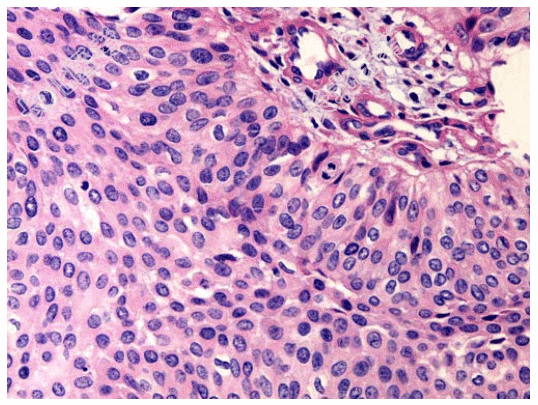

- [材料题] 男性,78岁,血尿2年。CT示右侧肾盂内可见软组织密度影,肾盂肾盏受压变形,考虑为肾脏肿瘤,遂行右肾切除,肾脏大体如图所示,镜检如图所示。临床考虑诊断为右肾盂移行细胞癌Ⅱ级。

- 1、该疾病镜下改变表现为?2、该疾病免疫